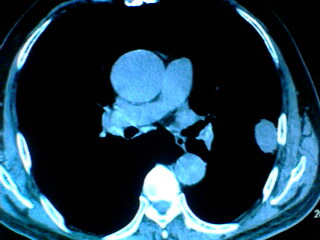

老年男性患者,右侧胸疼1月余(不是左侧),无其他症状

左肺外周类圆形病灶,其内低密度,可见液平及气影,周围肺文理见渗出样变,考虑左肺外周带肺脓肿。

支持肺囊肿,液体含量多,可能与支气管不通.右侧胸膜局限性肥厚,可能是导致痛的原因.

支持肺囊肿,右侧胸膜肥厚粘连钙化.

左肺舌叶胸膜下卵圆形囊性肿块,内有液-气平面,邻近胸膜无增厚,没有肺窗,周围情况显示不清,考虑胸膜下肺囊肿并感染,病人年龄较大,有胸痛应警惕其他,但神经源性肿瘤暂不考虑。